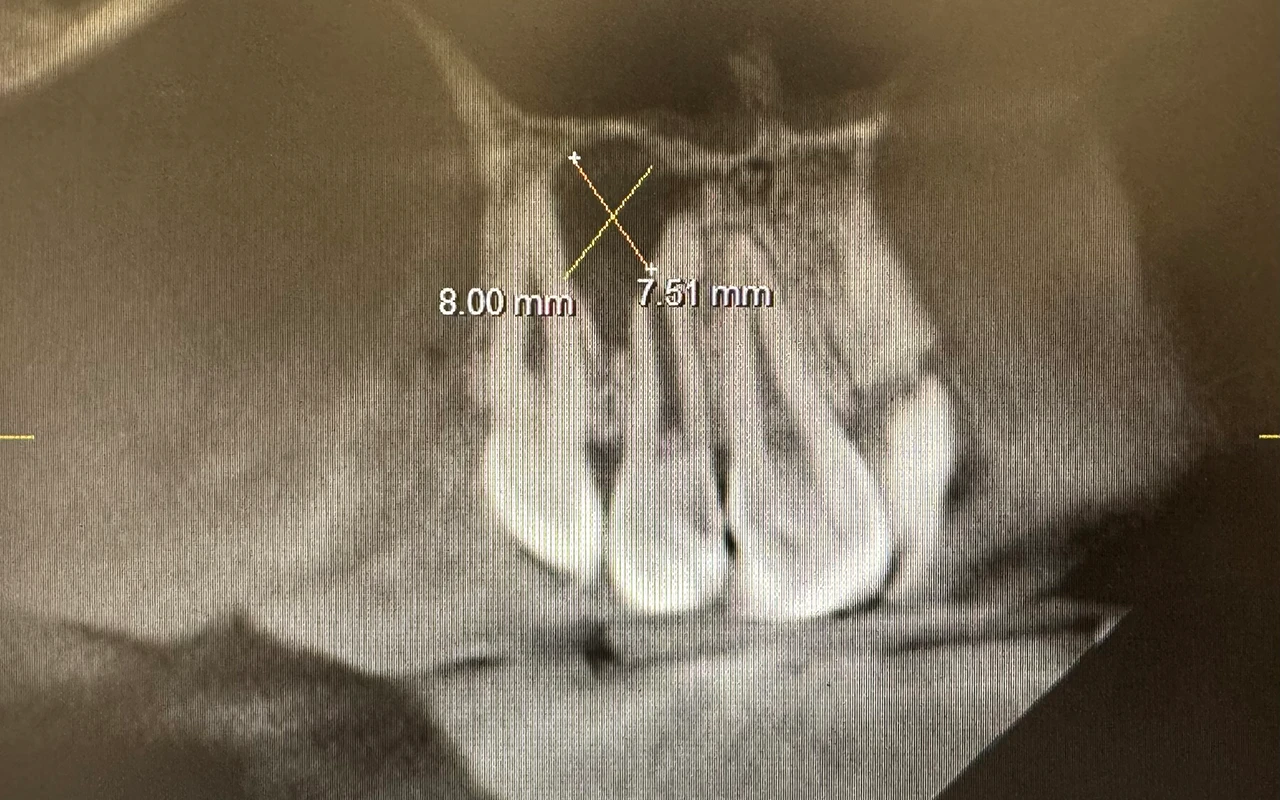

Неполная пломбировка корневых каналов

Представьте, что корневой канал — это узкий туннель внутри корня, который необходимо герметично закрыть после инструментальной и медикаментозной обработки. Неполная пломбировка — это когда часть этого туннеля осталась пустой, и со временем там могут накапливаться бактерии, способные вызвать воспаление и боль (особенно если обработка канала также была неполной). Иными словами — пломбировочный материал не дошёл до верхушки корня или заполнил не весь просвет корневого канала.

Бактерии, оставшиеся в плохо обработанных и незапломбированных участках каналов, способны вызывать или поддерживать существующее хроническое воспаление периодонта, и не всегда это сразу проявляется болью. Довольно часто, пытаясь изолировать инфекцию, организм образует вокруг верхушки проблемного корня кисту или гранулёму, которые со временем могут постепенно увеличиваться в размерах, разрушая костную ткань. Если проблему не выявить вовремя, это может привести к выраженной болевой реакции и даже к потере зуба.

Обычно в таких случаях проводится перелечивание корневых каналов. Врач-эндодонтист тщательно удаляет старый материал, полностью проходит и обрабатывает корневые каналы и заново пломбирует их на всю длину. Благодаря современным технологиям, стоматологическому микроскопу и рентген-контролю на всех этапах перепломбировки прогноз лечения обычно благоприятный.